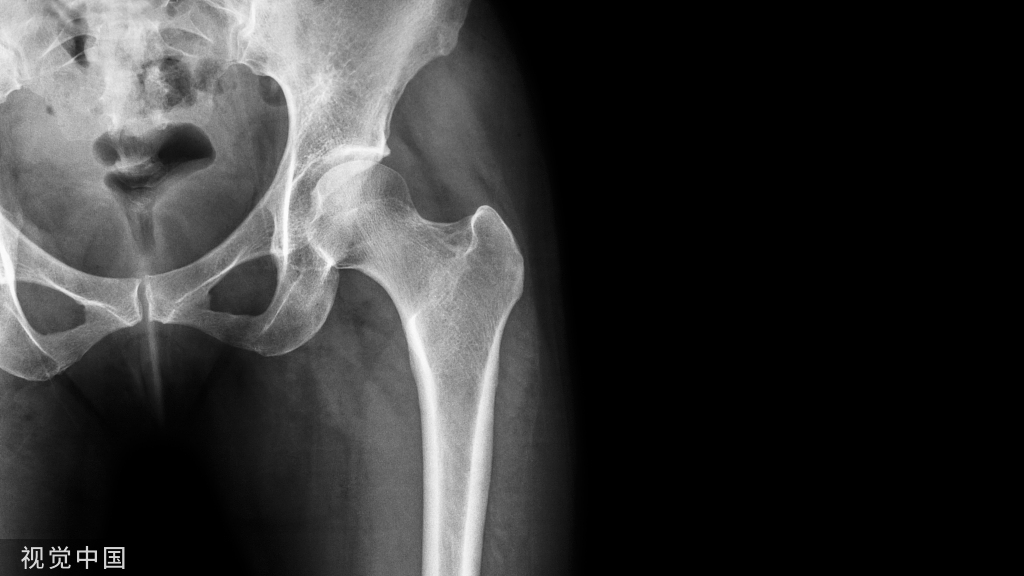

干骺端长斜形骨折采用髓内钉固定的难点之一为骨折对线的恢复,长斜形骨折由于骨折本身暴力方向、骨折周围肌肉的牵拉或远端肢体的重力因素,骨折断端间通常存在侧方移位趋势,由于髓内钉直径通常小于远端髓腔,直接置入后髓内钉在远端髓腔内可能存在摆动,因此在髓内钉置入时如何保持骨折远近端的对位对线是临床较为棘手问题。

Poller螺钉可以改变髓内钉方向、纠正骨折侧方移位,在长斜形骨折的髓内钉固定中使用越来越广泛。如何有效置入Poller钉,将Poller钉置于何处,显得尤为重要。既往对Poller钉置入存在诸多迷惑之处,如将Poller钉置于不想让髓内钉去的地方或者依据两短原则等,无明确理论支撑。本文简要介绍Poller钉的置入技术、改良技术,及其在下肢畸形矫形中的应用。一、Poller钉及髓内钉置入的“六步法”